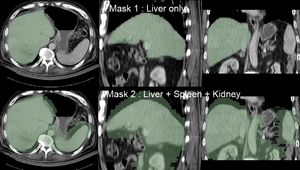

Note: for illustration the example set contains 2 masks: one with only the liver and one also including spleen and kidney (Mask2). As shown in the results below, the liver-only mask is insufficiently constraining the registration, yielding a result that at first glance looks ok for the liver, but has significant misalignment in the remaining abdominal area. Hence it is advisable to stabilize the registration further by including more structures with good contrast in both images (Spleen, Kidney).

registration masks